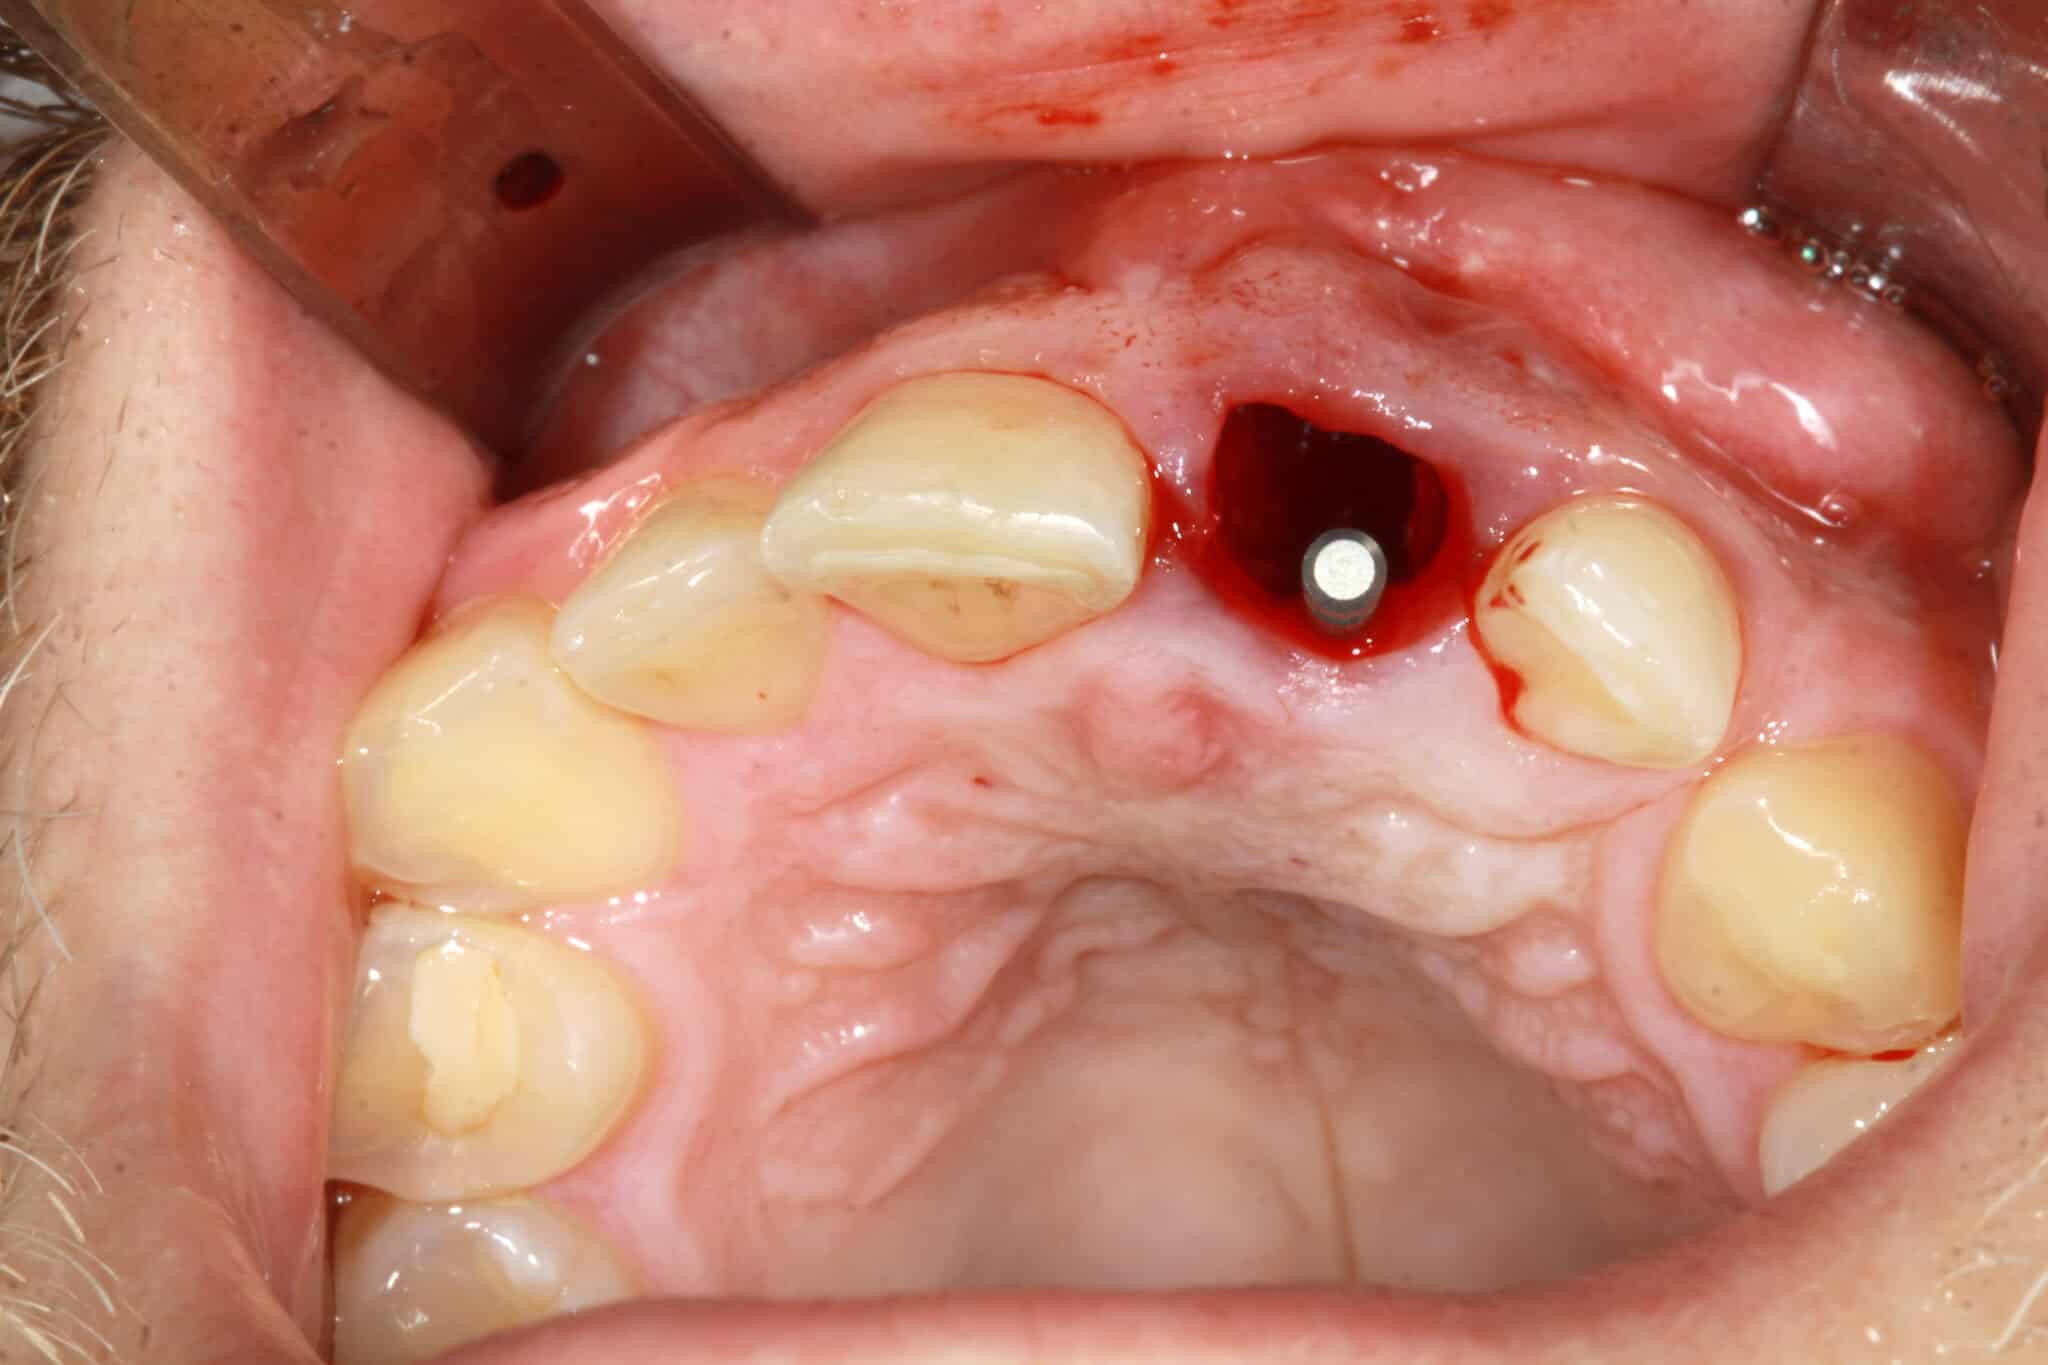

2. Après avoir soigneusement cureté la cavité alvéolaire, la position tridimensionnelle correcte de l’implant a été déterminée et le foret pilote a été positionné en direction palatine dans l’alvéole à trois parois entièrement intacte. La préparation du lit implantaire pour un implant CONELOG® PROGRESSIVE-LINE de 16 mm (Ø 3,8 mm) a été réalisée conformément au protocole chirurgical.

3. Une insertion primaire stable peut être réalisée car le corps conique apical de l’implant peut être entièrement ancré dans l’os local en raison de sa longueur. L’implant a été inséré avec un couple suffisant au contact de la paroi alvéolaire palatine. Le macro design de l’implant développé pour les protocoles de restauration immédiate a atteint une stabilité initiale élevée sur les cinq à six millimètres apicaux.